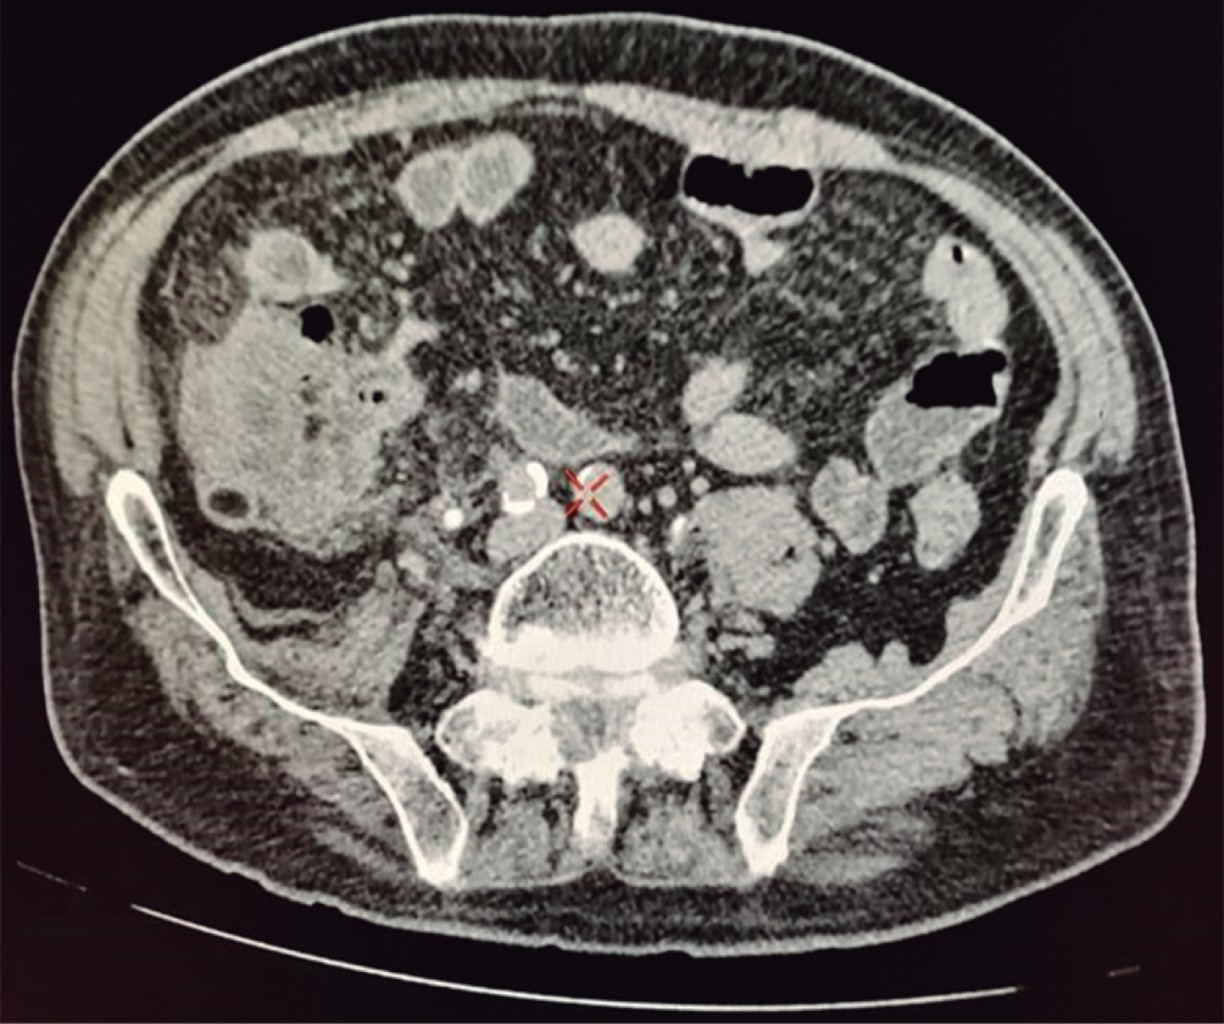

An 81 years-old male presented with a 72-hour abdominal pain evolution, predominantly at the level of the right iliac fossa (RIF), associated with an episode of bacteremia, hyporexia, nausea, vomiting and liquid stools. The abdomen was tender on palpation of the RIF with positive signs of appendix inflammation; hyperactive peristalsis was hard on auscultation and there was evidence of a peritoneal irritation syndrome. His lab tests showed leukocytosis of 11.2 × 103 uL with neutrophilia of 86.9%. An abdominal-pelvic tomography scan with intravenous contrast medium (Figure 1) showed the cecal appendix with data of an acute inflammatory process. Open appendectomy was performed by McBurney incision. Upon entering the abdominal cavity, three free peritoneal bodies were found incidentally, which were sent for histopathological study, together with the resected cecal appendix (Figure 2).

Figure 1